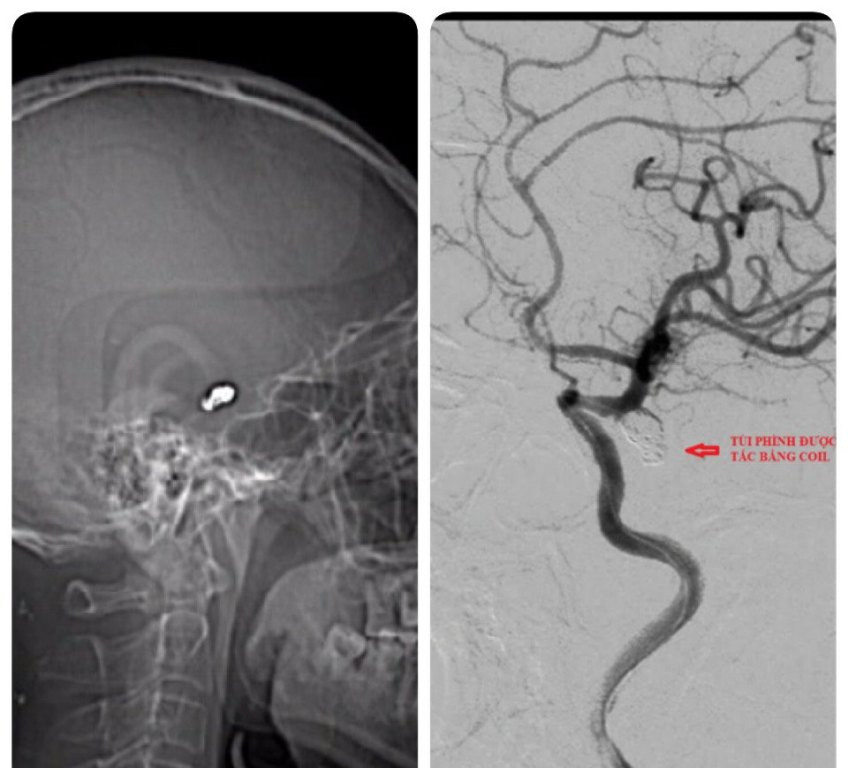

Vòng xoắn coils hiện diện trong não sau can thiệp (ảnh: BVCC) Các bác sĩ khoa Ngoại Thần kinh đã hội chẩn với lãnh đạo khoa và ekip can thiệp nội mạch. Nhận định đây là tình huống nguy hiểm, đe dọa tính mạng bệnh nhân do túi phình cảnh trong thông sau trái có khả năng tái vỡ, bệnh nhân được khẩn trương tiến hành can thiệp nội mạch bít tắc bằng các vòng xoắn kim loại (coils).

Bệnh nhân tỉnh táo sau phẫu thuật (ảnh: BVCC) “Một trong những phương pháp hiện đại nhất hiện nay là can thiệp nội mạch bít túi phình, đường rạch da chỉ 2 cm ở bẹn. Luồn một sơi dây đi trong lòng mạch máu đến túi phình và bỏ những vòng xoắn kim loại (coils) bít túi phình. Thời gian nằm viện và phục hồi tốt hơn phương pháp mổ hở hay vi phẫu thuật túi phình,” TS.BS Tuấn cho biết.